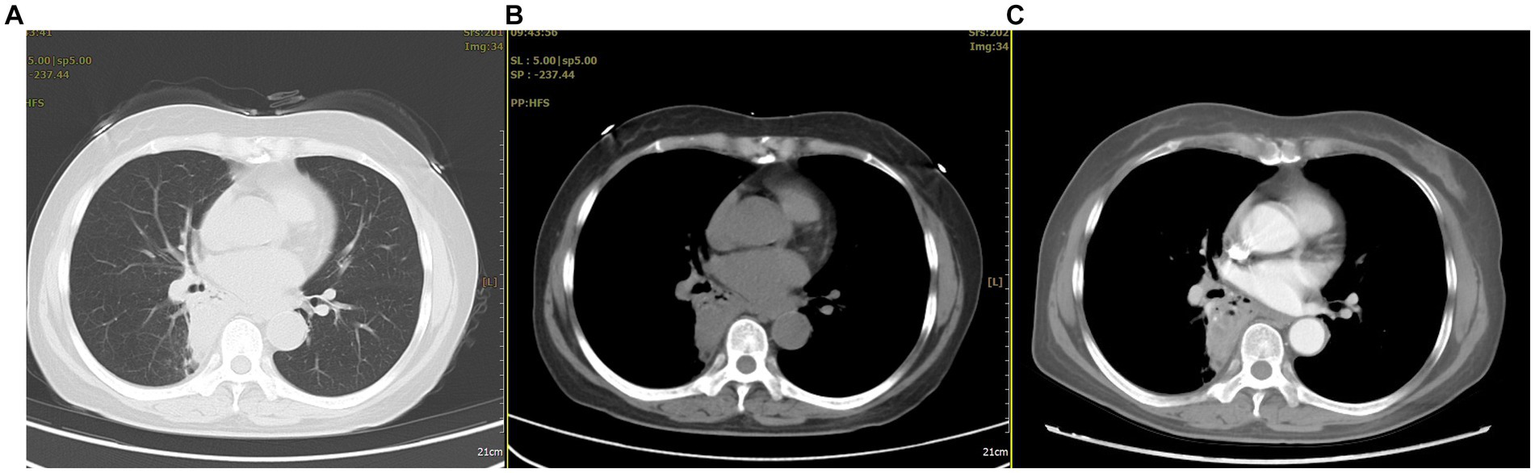

After admission, multiple laboratory tests were arranged. The patient’s white blood cell and neutrophil counts were 11.1*109/L and 7.1*109/L, respectively; her D-dimer level was 1.97 mg/L; her procalcitonin level was normal; and her tuberculin test and tumor-related indicators were negative. A chest CT showed a nodular shadow with a relatively regular morphology and uneven enhancement in the right lung (Figure 1).

Figure 1

The chest CT revealed abnormal lesions in the lower lobe of the right lung. (A) In the lung window, a consolidation shadow was observed in the posterior segment of the right lower lobe. (B) In the mediastinal window, the lesion appeared to have regular margins. (C) After contrast enhancement, heterogeneous enhancement was noted within the lesion.